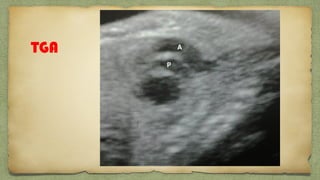

TGA

๏ฑThe ultrasound beam is directed

perpendicular to the midchest

plane at the level of the heart.

๏ฑ These chambers consist of the

right and left atrial and both

ventricular chambers

๏ฑCorresponding valves between

them

Four-Chamber View

On Slight angulation

Towards rt shlder

Short-axis

view

Grt Vs

Toward Lt shoulder

Apical 5

chamber

Cephalad direction

3 Vs &

Trachea